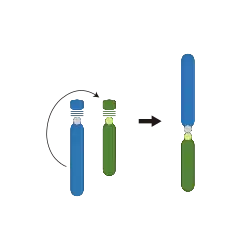

- Inversions: A portion of the chromosome has broken off, turned upside down, and reattached, therefore the genetic material is inverted.[1]

- Translocations: A portion of one chromosome has been transferred to another chromosome.[1] There are two main types of translocations:

- Reciprocal translocation: Segments from two different chromosomes have been exchanged.[21]

- Robertsonian translocation: A pair of chromosomes break at their centromeres, lose their short p arms, and fuse at their q arms, forming a single chromosome with one centromere.[1] This type of translocation typically occurs between chromosomes 13, 14, 15, 21, and 22 in humans.[21]